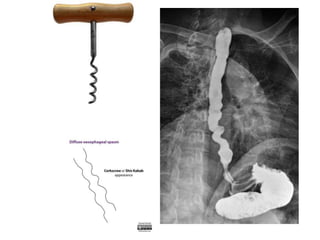

Barium swallow

• test of the pharynx, esophagus, and proximal stomach,

• may be performed as a single or double contrast study.

• The study is often "modified" to suit the history and

symptoms of the individual patient, but it is often

useful to evaluate the entire pathway from the lips to

the gastric fundus.

• Upper GI endoscopy (UGIE or EGD) has largely replaced

the barium swallow for the assessment of peptic ulcer

disease and the evaluation of hematemesis.

Barium swallow • testof the pharynx, esophagus, and proximal stomach, • may be performed as a single or double contrast study. • The study is often "modified" to suit the history and symptoms of the individual patient, but it is often useful to evaluate the entire pathway from the lips to the gastric fundus. • Upper GI endoscopy (UGIE or EGD) has largely replaced the barium swallow for the assessment of peptic ulcer disease and the evaluation of hematemesis.